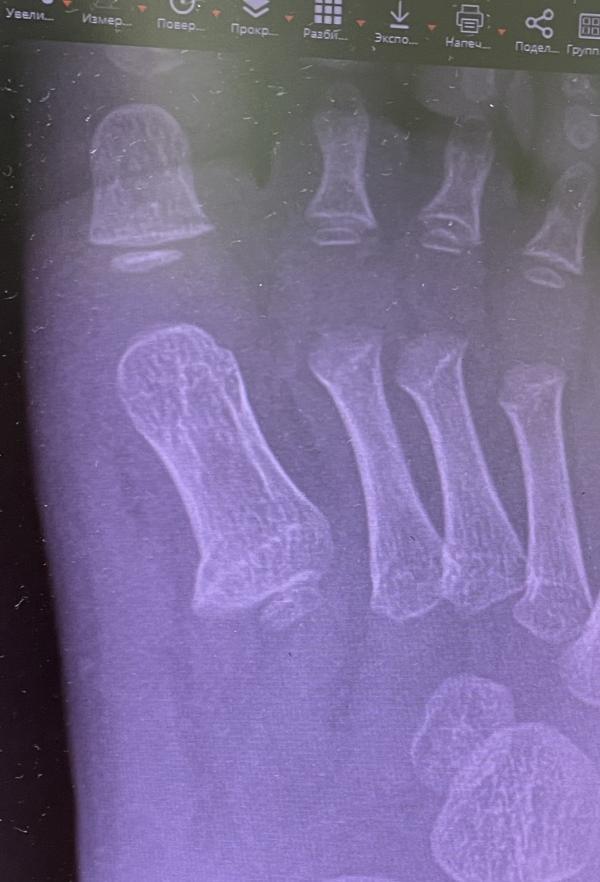

Перелом кости фаланги